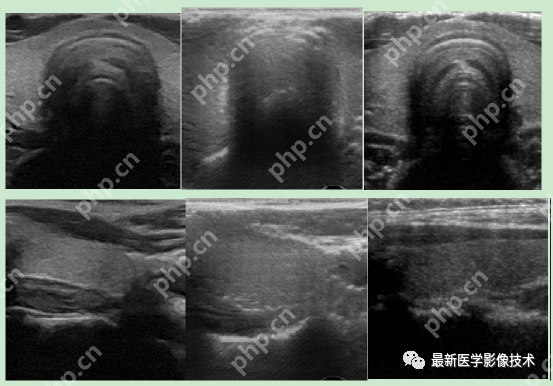

6、测试集部分生成结果

左图为低质量图像,右图为生成的高质量图像。